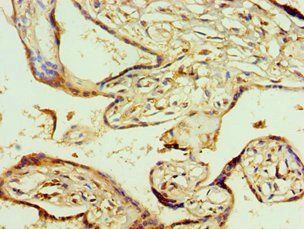

Immunohistochemical analysis of G15 staining in human breast cancer formalin fixed paraffin embedded tissue section. The section was pre-treated using heat mediated antigen retrieval with sodium citrate buffer (pH6.0). The section was then incubated with the antibody at room temperature and detected using an HRP conjugated compact polymer system. DAB was used as the chromogen. The section was then counterstained with haematoxylin and mounted with DPX.